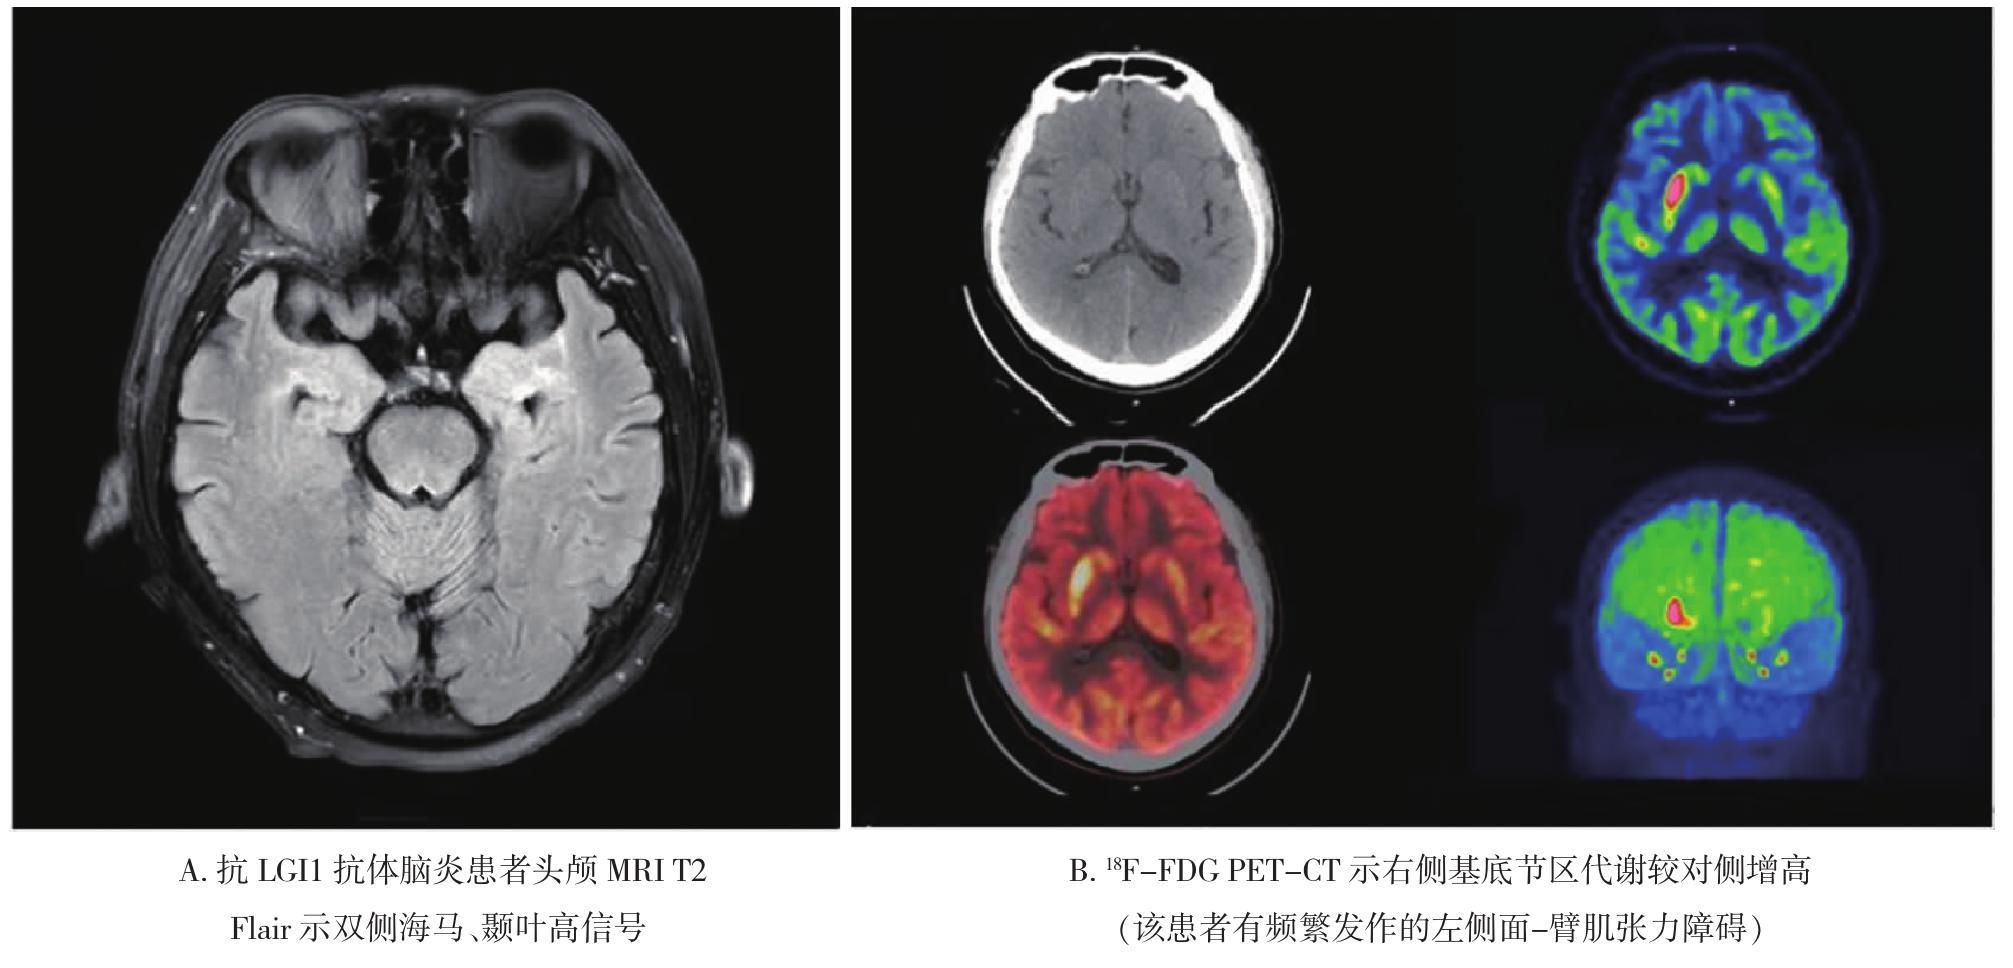

• 自身免疫性脑炎的诊断进展

2021, 46(7):754-759. DOI: 10.13406/j.cnki.cyxb.002867

摘要 (140) HTML (295) PDF 2.06 M (243) 评论 (0) 收藏

摘要:自身免疫性脑炎主要表现为急性或亚急性记忆障碍、精神行为异常及癫痫发作。2016年Lancet Neurolgy发表的自身免疫性脑炎临床诊断标准及排除标准及2017年中华医学会神经病学分会发布的《中国自身免疫性脑炎诊治专家共识》为我国自身免疫性脑炎规范化诊疗提供了重要参考。本文就临床常见的自身免疫性脑炎类型及近些年新发现的自身免疫性脑炎抗体相关综合征的临床特征作一总结,为自身免疫性脑炎的诊断提供思路。